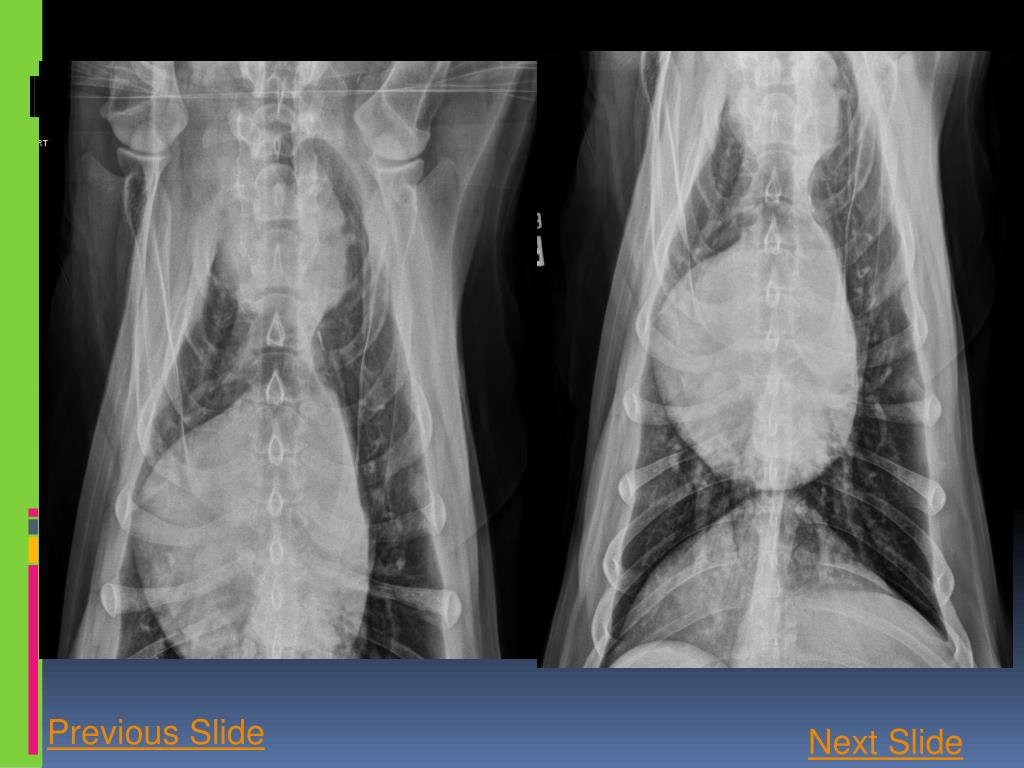

4. Previous Slide Next Slide

5. Next Slide Previous Slide

7. Based on your assessment of the radiographs, the thoracic body wall (including the osseous structures and portion of the cranial abdomen included in the collimation) is: • Abnormal • Normal

8. Correct! There areS4-5 subluxation (white circle) and multifocal sternebral degenerative changes. Next Slide

18. Correct! • In the cranioventralmediastinal reflection, just dorsal to the second sternebra, there is a 7.5 cm round, well-defined soft tissue opaque mass which causes widening of the cranial mediastinum. Continue

21. Correct! There is mild diffuse reticular to linear increase in soft tissue opacity throughout the lung lobes, that partially hampers the evaluation of the pulmonary vasculature. Next slide

22. Conclusion Your findings now include: • Cranioventralmediastinalmass • Mild diffuse unstructured interstitial pulmonary pattern – more likely due to senile pulmonary interstitial fibrosis • Possible S4-5 subluxation and multifocal sternebral degenerative changes. • What are your differential diagnosis for the cranioventralmediastinal mass? click next.